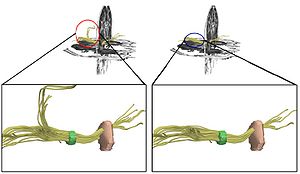

Publication: J Neurosurg. 2016 Jan 1:1-8. PMID: 26722859 Authors: Song F, Hou Y, Sun G, Chen X, Xu B, Huang JH, Zhang J. Institution: Department of Neurosurgery, People's Liberation Army General Hospital, Beijing, China. Background/Purpose: OBJECTIVE Preoperative determination of the facial nerve (FN) course is essential to preserving its function. Neither regular preoperative imaging examination nor intraoperative electrophysiological monitoring is able to determine the exact position of the FN. The diffusion tensor imaging-based fiber tracking (DTI-FT) technique has been widely used for the preoperative noninvasive visualization of the neural fasciculus in the white matter of brain. However, further studies are required to establish its role in the preoperative visualization of the FN in acoustic neuroma surgery. The object of this study is to evaluate the feasibility of using DTI-FT to visualize the FN. Methods Data from 15 patients with acoustic neuromas were collected using 3-T MRI. The visualized FN course and its position relative to the tumors were determined using DTI-FT with 3D Slicer software. The preoperative visualization results of FN tracking were verified using microscopic observation and electrophysiological monitoring during microsurgery. Results Preoperative visualization of the FN using DTI-FT was observed in 93.3% of the patients. However, in 92.9% of the patients, the FN visualization results were consistent with the actual surgery. CONCLUSIONS DTI-FT, in combination with intraoperative FN electrophysiological monitoring, demonstrated improved FN preservation in patients with acoustic neuroma. FN visualization mainly included the facial-vestibular nerve complex of the FN and vestibular nerve. |

2015